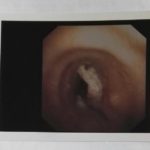

8 Marzo 2017Cassino – Importante intervento eseguito all’ospedale “Santa Scolastica” di Cassino. Si tratta di un intervento eseguito in endoscopia bronchiale dall’equipe guidata dal Dott. Filippo Di Ruzza. Il paziente 76enne, di nazionalità straniera, arriva all’Ospedale Santa Scolastica di Cassino in urgenza con una grave affezione oncologica che potrebbe rivelarsi fatale: non respira, l’affezione oncologica gli blocca la trachea. (foto 1)

Al primo controllo in trachea lo spazio per respirare, per via della vicinanza delle parti aggredite dal male, si è di nuovo ridotto. Il paziente di lì a poco (qualche giorno, se non proprio ore) potrebbe venir meno.